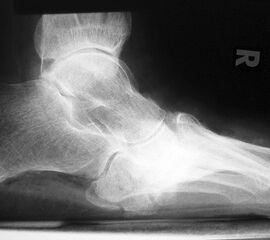

Abbildung 2

DNOAP Typ I (Abb. 2):

Hierbei handelt es sich um Nekrosen der Interphalangeal-, Metatatarsophalangealgelenke und Metatarsalia, was es zur knöchernen Resorption an den Mittelfußköpfchen und Zehengliedern führt. Die Stummel der Metatarsalia gleichen abgelutschten Zuckerstengeln, bohren sich in der Abstoßphase in die Sohle und führen zum Malum perforans.